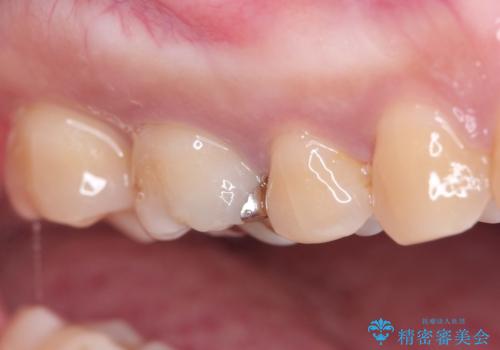

- 虫歯の治療を主訴に来院されました。メタルフリーによる治療を希望されましたので、セラミックインレーにて修復治療を行っております。

当院でのセラミックインレーはすべてe-maxと呼ばれる高強度セラミックにて製作されます。

また、製作方法もプレスと呼ばれる方法を用いることで精度を高めています。